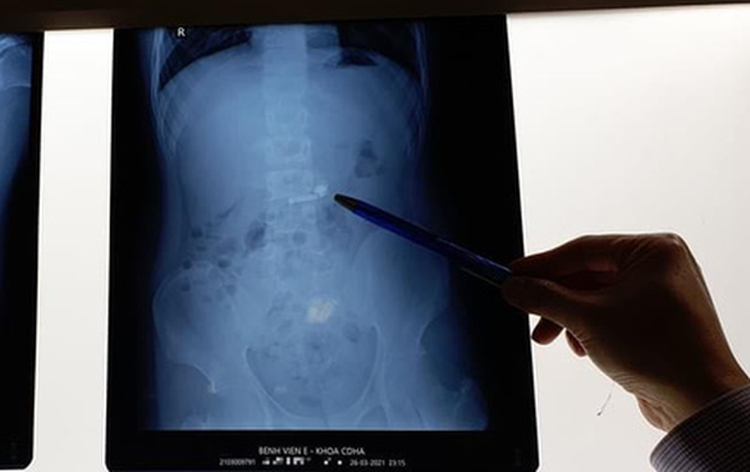

The Emergency Department of E Hospital in Hanoi recently successfully removed a wireless earbud from the abdomen of a 15-year-old patient.

X-ray results showed that there was an earbud in the abdomen of the child.

It was not until 2:50 am the next day that Dr. Nguyen Van Thanh of the hospital’s hepatobiliary department managed to perform the flexible bronchoscopy with general anesthesia to successfully pick up the foreign object from the child.